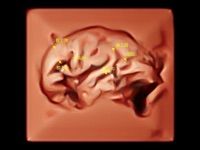

作為開(kāi)立醫(yī)療全新打造的超高端旗艦超聲產(chǎn)品,從探頭抬起喚醒開(kāi)啟掃查到多維探頭發(fā)射接收,通過(guò)先進(jìn)的場(chǎng)成像發(fā)射、自適應(yīng)聚合重建等技術(shù),基于RF Data原始射頻數(shù)據(jù)在圖像生成、高端功能等方面實(shí)現(xiàn)突破,為婦產(chǎn)科、兒科提供全方位臨床解決方案。

獨(dú)有場(chǎng)成像發(fā)射技術(shù)

自適應(yīng)聚合重建技術(shù)

獨(dú)家XPUs混合硬件架構(gòu)